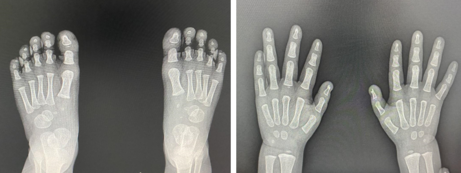

Al examen físico del recién nacido, llama la atención la apariencia de las uñas de las manos y de los pies. Ambas manos y pies presentaban una ausencia de las uñas en el digito 2, con hipoplasia ungueal de los dígitos 2 y 3 y respetando los dígitos 4 y 5 completamente normales. ( Figura 1) Resto del examen físico de piel y faneras sin alteraciones evidentes. La radiografía no mostro ninguna alteración esquelética ( Figura 2).

La historia familiar resalta por hallazgos similares en la madre, abuela y una de las hermanas del paciente. Todos los comprometidos no refieren ninguna alteración en su ritmo de vida o problemas en actividades cotidianas secundarias a dicha alteración ( Figura 1 y 3).